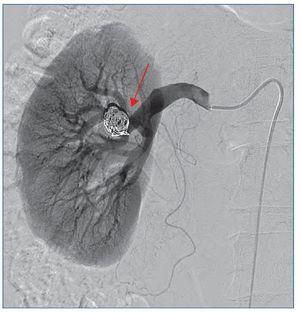

Se realiza arteriografía con sustracción digital intraarterial, que confirma el aneurisma en la rama inferior de la bifurcación posterior de la arteria renal derecha de 11,4 × 15,8 mm de diámetro (figura 2).

Figura 2. Arteriografía que confirma el aneurisma en la rama inferior de la bifurcación posterior de la arteria renal derecha.